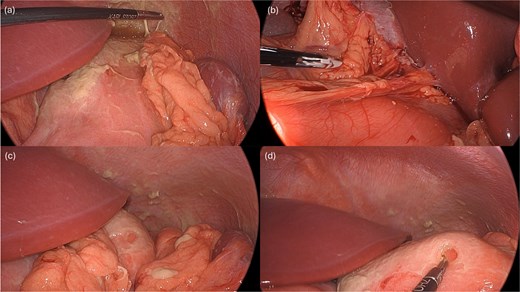

A leak test was then performed by submerging the repair site under saline and endoscopically insufflating the stomach; no bubbling was noted, indicating a successful seal. The repair was reinforced with an omental patch, secured laparoscopically with a 2–0 silk suture (Fig. 4). A single drain was left in the abdomen, remaining fluid was suctioned. Endoscopic biopsies of the stomach and duodenum were obtained, and a nasogastric tube was placed.

Following endoscopic closure, a leak test performed under water (a) did not demonstrate any bubbling after gastric insufflation with air. Photos (b–d) demonstrate performance of a graham patch with a redundant lip of omentum over the endoscopically closed perforation.